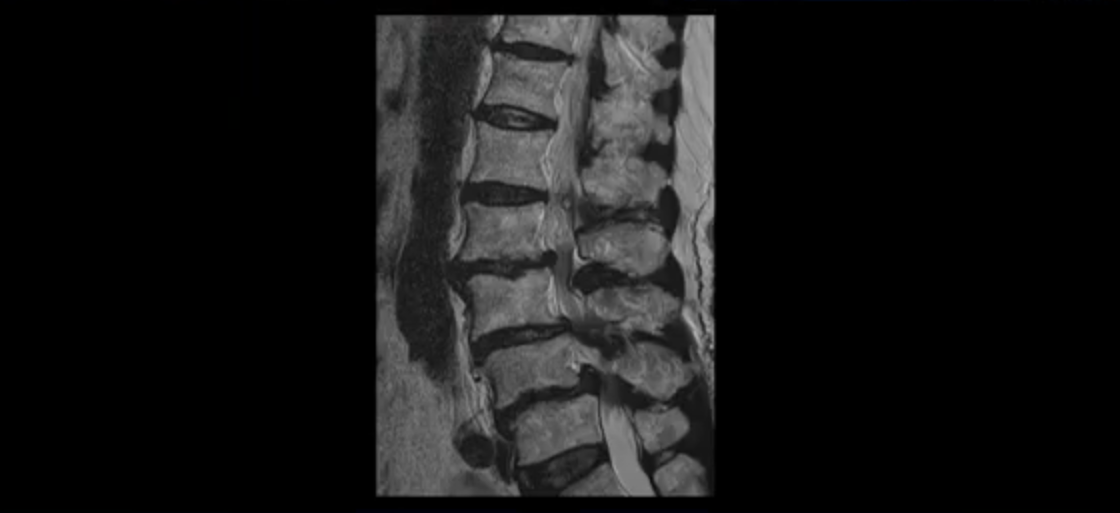

이 환자분 MRI를 보면서 더 자세히 설명 드리겠습니다. 이분은 허리의 다섯 마디가 다 안 좋은 환자분입니다. 84세 고령의 나이에 이렇게 여러 마디가 안 좋으면 대학병원에서도 수술이 어렵다는 얘기를 듣는 경우가 많습니다. 또 수술을 하더라도 결과가 안 좋을 수 있다는 얘기를 들을 가능성이 높습니다.

보시다시피 허리 다섯 마디 전부가 다 퇴행되어 있고,

두 마디에 전방전위증이 있고,

2번 3번,

3번 4번,

4번 5번에 중심성 협착이 심하고

거의 모든 추간공 즉, 신경가지가 좌우로 빠져나가는 구멍이 다 좁아져 있습니다.

척추가 이런 상태니까 양쪽 엉치와 다리가 다 저리고 아프며 지팡이를 짚고 겨우 걷는 상태였습니다. 이렇게 국내 최상위 대학병원에서도 수술하지 말라고, 수술하면 더 안 좋을 거라는 얘기를 들은 고령의 말기 협착증 환자가 근육 재활치료로 좋아질 수 있을까요? 당연히 좋아질 수 있습니다. 무슨 근거로 이렇게 자신있게 얘기하는 걸까요? 왜냐하면 근육이 좋아지는 만큼 협착증 증상이 좋아지기 때문입니다. 근육은 뭉친 걸 반복해서 풀어주고 환자 상태에 맞는 적절한 운동을 잘 하는만큼 좋아질 가능성이 매우 높습니다. 저희는 수많은 치료 후기와 임상시험을 통한 국제학술 논문 등을 통하여 이렇게 여러 마디가 안 좋은 고령의 말기 협착증 환자분들도 근육을 치료하여 근육 상태가 좋아지면 협착증 증상이 좋아진다는 걸 계속해서 보여드리고 있습니다.